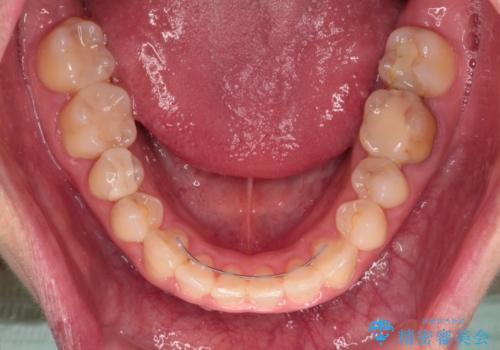

捻れていた前歯の形態が、先端が欠けていたり、一部むし歯処置により左右非対称の形態となっていたため、なかなかゴールが定まらず、治療期間がかかってしまいました。